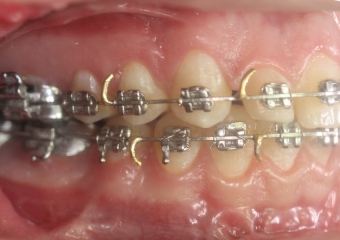

Mordida inicial